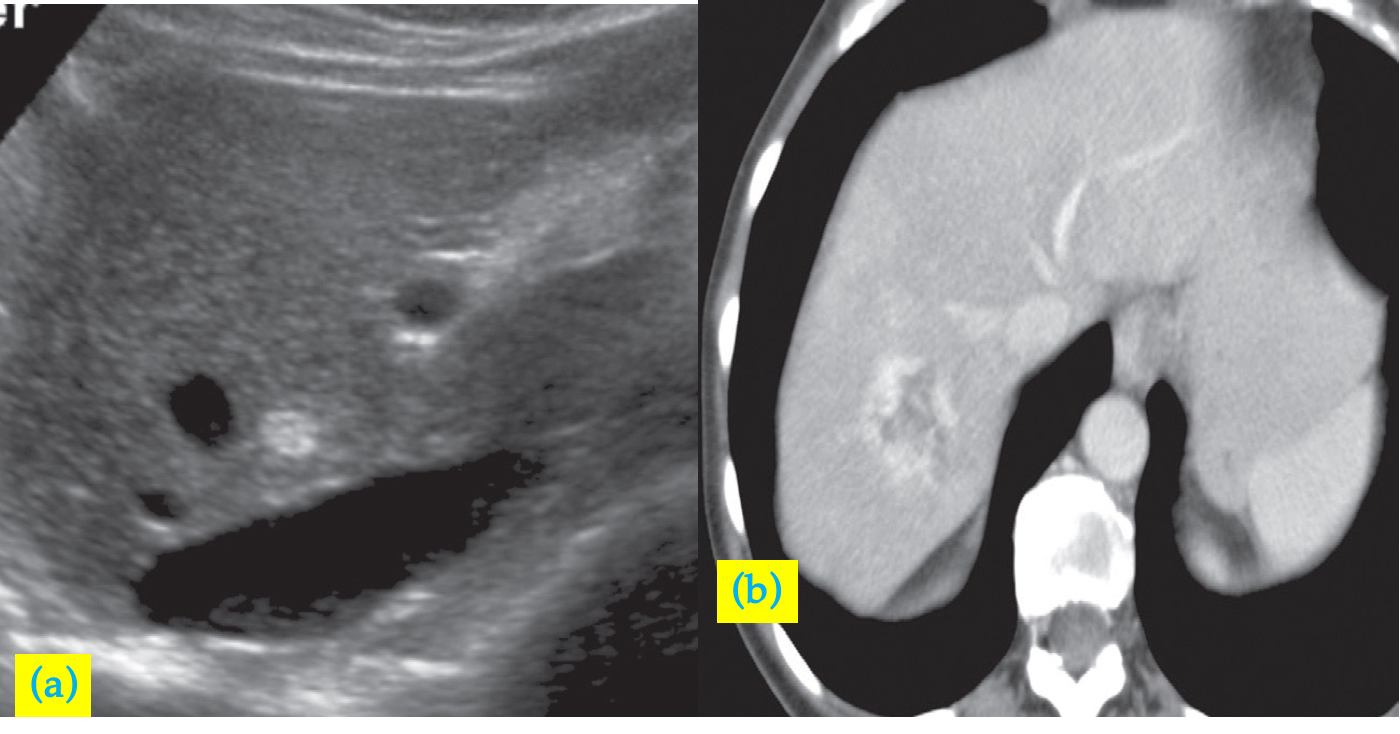

At ultrasound, haemangiomas are typically well-defined, peripheral, echogenic masses z

At CT, there is usually a characteristic enhancement pattern characterized by sequential contrast opacification, beginning as nodular or globular areas of enhancement at the periphery and proceeding toward the centre over time until the density increases to become similar to that of the surrounding liver. Haemangioma (incidental finding).

• (a) Ultrasound scan showing an echogenic mass in the right lobe of the liver . IVC, inferior vena cava.

• (b) CT scan, in another patient, after intravenous contrast enhancement showing a low density lesion in the right lobe of the liver with peripheral nodular enhancement, characteristic of a haemangioma.